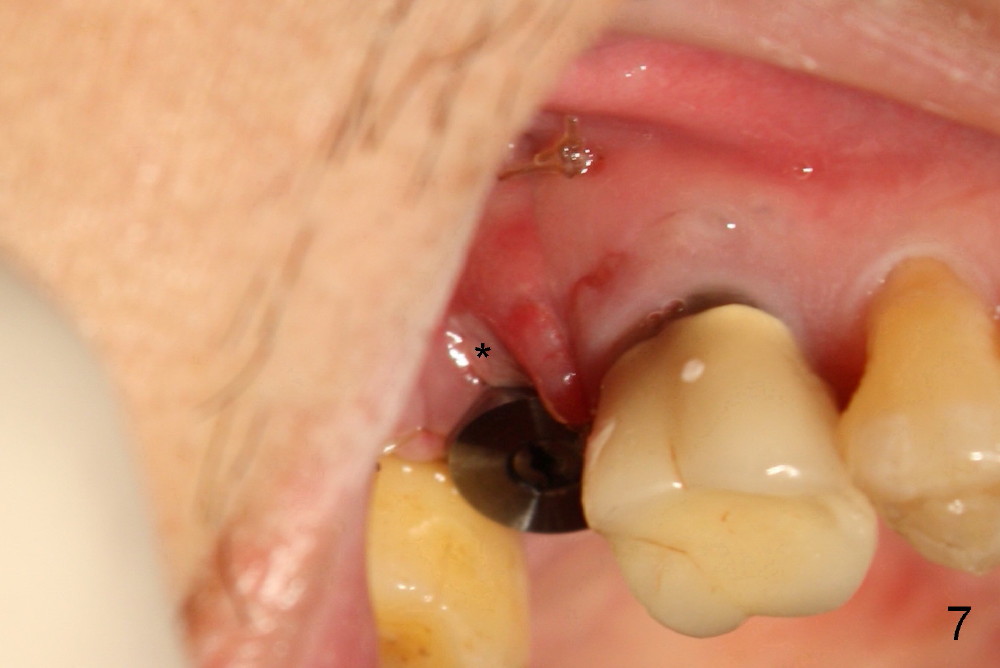

The 60-year-old man is a bruxer. All of the three upper right molars are nonsalvageable (Fig.1). Since #2 is symptomatic, it is planned to be extracted and restored first. As expected, there is severe alveolar destruction (single large socket), while the base bone is solid. A series of tapered osteotomes (2-5 mm) are used to create osteotomy in the base bone (gaining 4 mm into new bone), followed by 4.5x20 mm tap at the depth of 17 mm from the gingival margin (Fig.2). Then the depth is adjusted to 14 mm; the bone expansion and osteotomy continue until using 7 mm tap with good binding to the bone (Fig.3). A 7x14 mm implant is placed with insertion torque more than 60 Ncm (Fig.4). No bone graft is used for sinus lift considering sinus membrane perforation. The buccal flap is raised to reveal bony defect, which is covered by Osteogen (a synthetic bone graft) and then collagen membrane (Fig.6 *). Five days postop, the membrane undergoes a type of transformation (Fig.7 *) leading to a gingival tissue (Fig.8 *, 18 days postop). By 3 months, the gingiva has normal appearance (Fig.9), while the implant seems to be osteointegrated (Fig.10). Once the infected source is removed, our body has potential to regenerate.

The patient complains food impaction between #1 and 2, six months post cementation. The former has mobility II. Although there is keratinized gingiva buccal to these sites (Fig.12), there is no papilla buccally (Fig.13) or palatally (Fig.14). The palatal pockets between #1 and 2 are deep with tenderness. X-ray shows bone loss between the sites (Fig.11 white *); the periodontal explorer can be felt to touch the distal implant threads (<). Extraction and immediate implant are recommended for #1. Twelve months later, the patient agrees with the treatment plan. The tooth #3 needs extraction and immediate implant, 2.5 years after the one at #2.